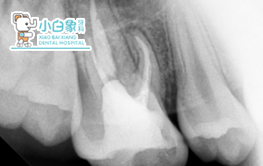

2月份根尖外科病例

2019.02.20

患者:***女 34y主诉:两侧后牙进食不适数日 现病史:数日前患者自觉双侧后牙进食不适,来诊要求检查,6年前曾于外院“抽牙神经”治疗,具体不详。既往史:体健。